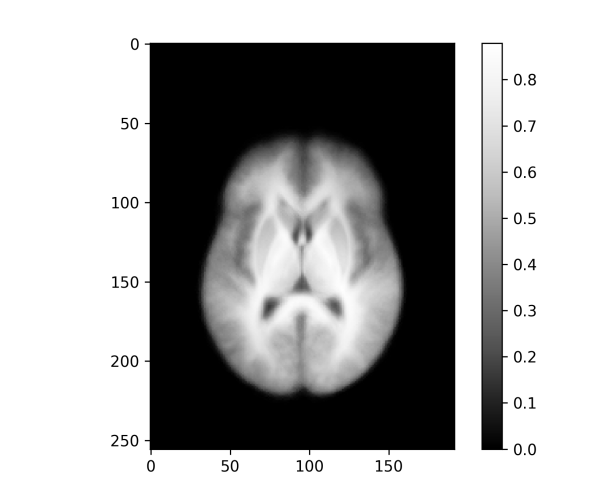

An important application of image registration is the preprocessing of 3d MRI brain images. Here a collection of brain images (possibly from different subjects) are registered with a template, here also called an atlas, which enables more direct comparisons between different brains despite differences in the respective brain geometry before registration. The dataset used here for demonstration purposes is the Neurofeedback Skull-stripped (NFBS) dataset [9], which contains 125 raw MRIs and their skull stripped versions. The intensities of the sample images are normalized such that the median of each image (without the background zeros) is mapped to . Additionally, we are optimizing an intensity scaling factor for each image during the registration such that the scaled template matches the registered image under the similarity metric. This minimizes the vertical variability and brings us a bit closer to the model situation of the shifted edges. The effective height for the resolution measure is chosen as .

For the skull stripped brains a template is generated for affine and rigid transformations and for - and -norm similarity measures, as shown in Figure 10. In each of the four cases the template resolution is computed with Algorithm 1 and horizontal slices of the resulting 3d images of the values are shown in Figure 11 and visualized on top of the template, as described in Subsection III-D, in Figure 12.

Again, the affine registration is more accurate, especially at the boundary of the brain, and the -norm templates appear sharper than the -norm versions but – as revealed by the template resolution measure – are only slightly better in terms of registration accuracy. The rigid registration results are almost identical. In the affine case the -norm leads to better registration at the upper part of the brain (frontal lobe; see Figure 2 for locations), while being similarly inaccurate around the lateral ventricles (twin holes in the lower middle). In all cases the regions in the upper middle of the brain (around the putamen and thalamus) are quite well registered and are also the sharpest regions of the templates across all registration variants. This is in agreement with measurements of the volumes of these brain regions (see e.g. Table 4 in [11] for healthy controls, or Table 2 in [12]) where the coefficients of variation (standard deviation divided by the mean) of the volumes are relatively low for the putamen and thalamus compared with those for the lateral ventricles, the latters’ variability ranging among the highest across all measured regions.